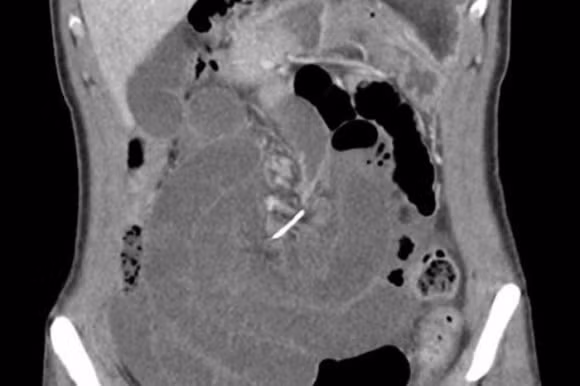

Một người phụ nữ 30 tuổi ở Úc đã phải nhập viện khi bị đau bụng dữ dội. Ban đầu, các bác sĩ chẩn đoán rằng, người phụ nữ này có thể có sỏi mật hoặc bị một mảnh xương cá chặn ngang ống mật. Tuy nhiên, kết quả chụp CT cho thấy một sợi dây kim loại mảnh dài 7cm đã đâm thủng ruột non của người bệnh ở nhiều chỗ. Do bị đâm vào nhiều chỗ, ruột non của người phụ nữ này đã bị xoắn xung quanh, gây ra hiện tượng được gọi là xoắn ruột non. Điều này cộng với nỗi đau cực độ mà người bệnh phải trải qua khiến các bác sĩ phải đưa ra quyết định là phẫu thuật.

Suốt 10 năm kể từ ngày niềng răng, người phụ nữ này không nhớ mình đã nuốt sợi dây kim loại hay mảnh kim loại nào ở chiếc niềng răng. Được biết, người phụ nữ sau đó đã hồi phục hoàn toàn sau ca cấp cứu và không gặp những tổn thương phụ khác.